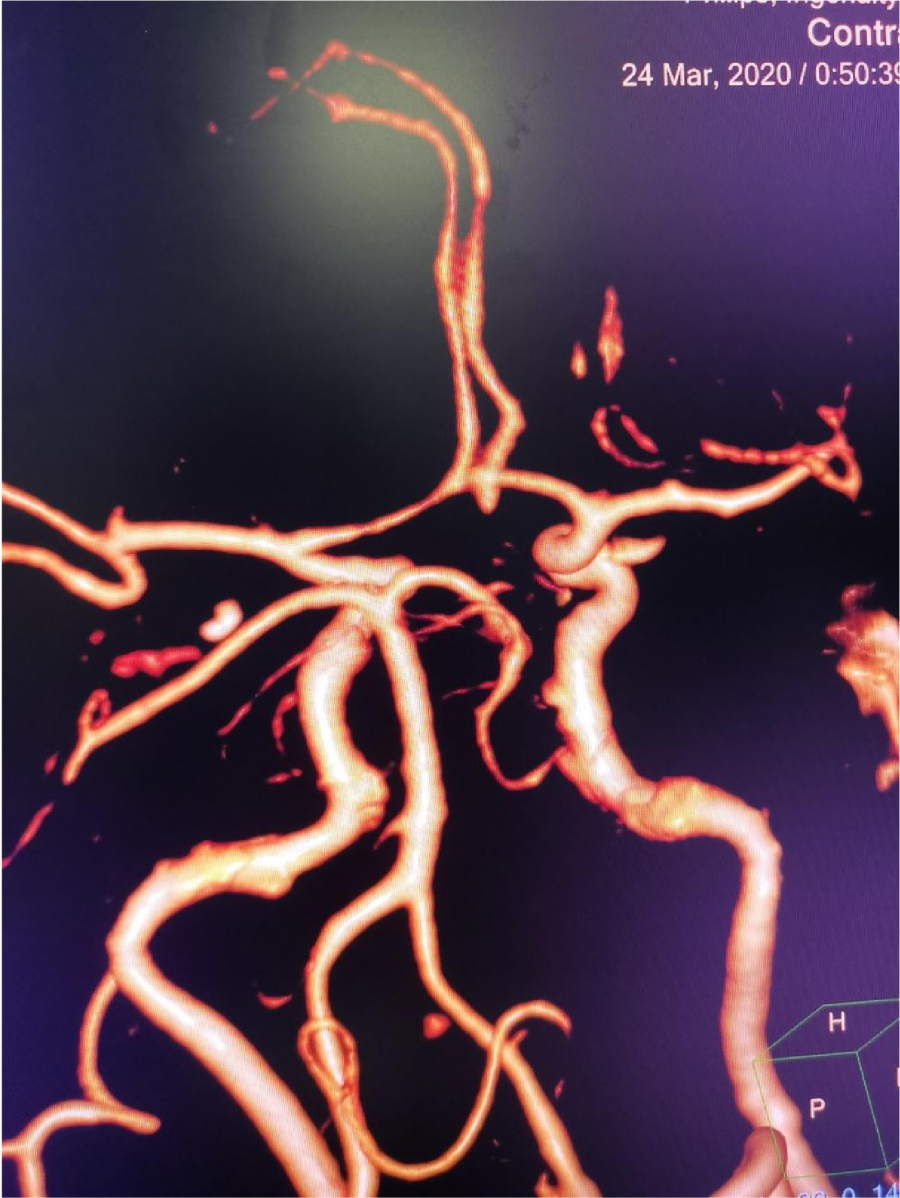

CTA 结果

本次⼊院⾏DSA检查:PICA供⾎区有畸形⾎管团,引流到横窦

术后CTA显⽰

术后CTA显⽰:畸形⾎管团消失